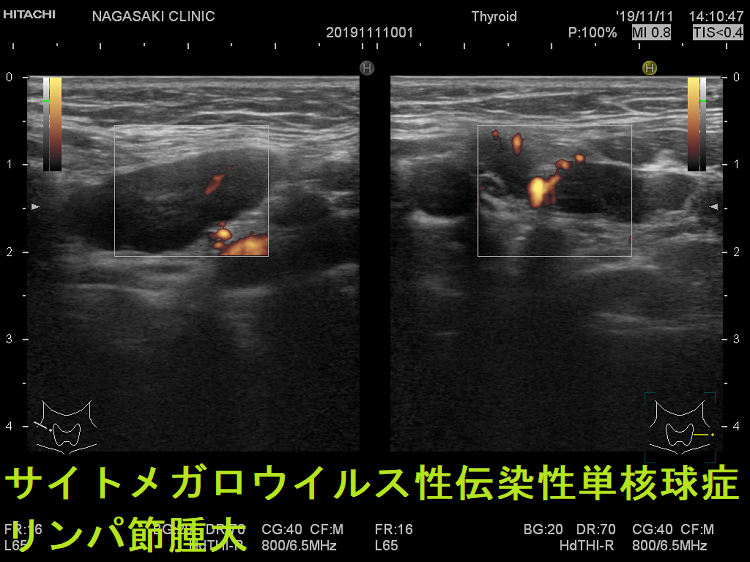

- 痛みを伴う著明な後頸部リンパ節腫脹は1〜2週頃がピークで、耳下腺の下、外側頚部まで累々と広がり、全身のリンパ節も腫大します。

- 亜急性甲状腺炎と鑑別を要する伝染性単核球症を発症